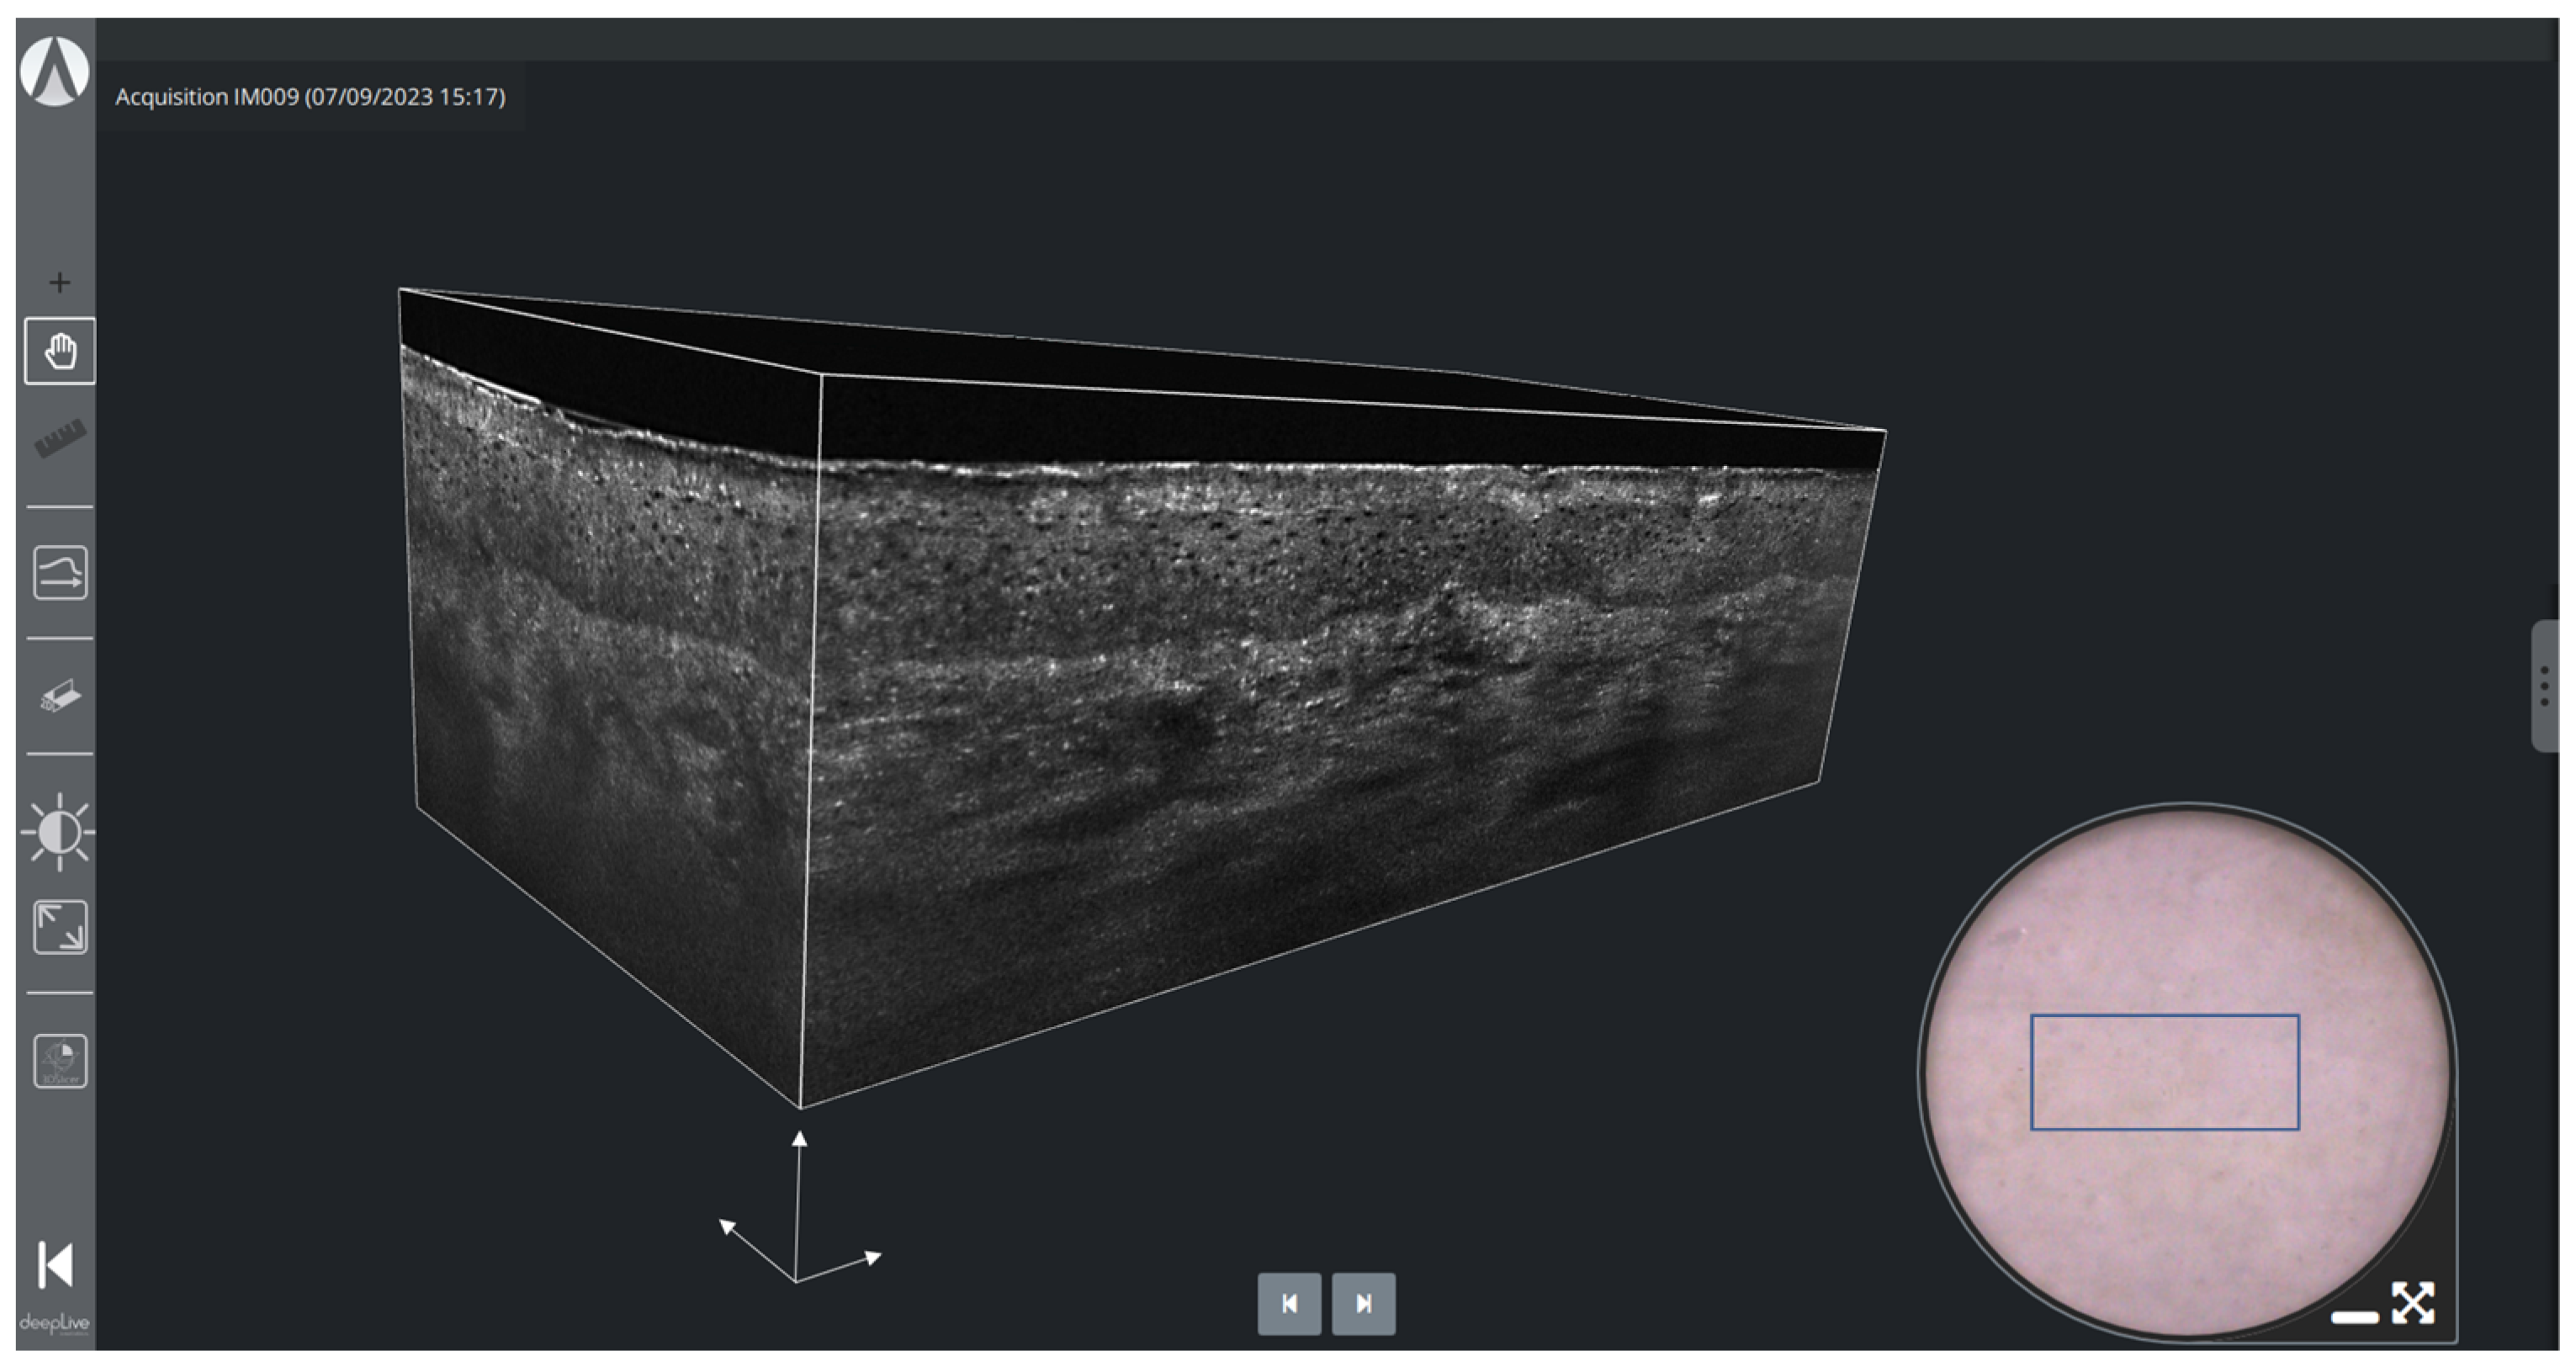

2.1.1. deepLive™

2.2.3. Three-Dimensional Imaging

- Ogien, J.; Daures, A.; Cazalas, M.; Perrot, J.L.; Dubois, A. Line-field confocal optical coherence tomography for three-dimensional skin imaging. Front. Optoelectron. 2020, 13, 381–392. [Google Scholar] [CrossRef] [PubMed]